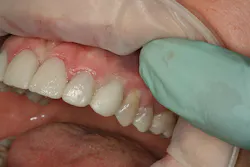

The provisionals were then removed and the gingival contact areas of Nos. 6 and 11 were modified with a flowable composite material to support the soft tissue and develop a more natural emergence profile3 (figures 7, 8). When appropriate support was achieved, the gingival contact areas of the provisional were polished to a smooth shine, free of rough areas. The provisionals were then trimmed, contoured, stained with tints, polished, and glazed (Luxaglaze, DMG America) prior to seating with a clear resin cement (TempBond Clear, Kerr). The patient was given home-care information and instructed to return in two weeks to evaluate the provisional restorations and tissue response around the implant sites.

During the two-week evaluation appointment, the tissues were determined to be responding appropriately (figure 9). Had they not, the provisionals would have been removed and modified before reseating and appointing for another two-week evaluation. As the tissue in this case was responding as expected, the patient was appointed to return in another two weeks for master impressions.